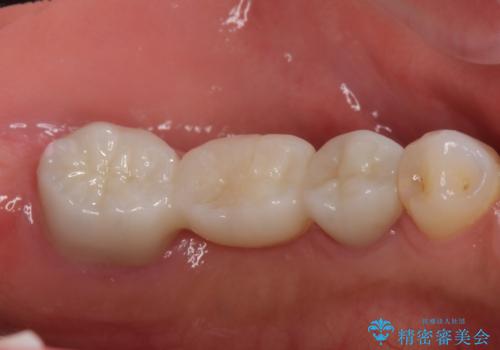

左下6番は残根状態だったため、やむなく抜歯を行い、⑤6⑦ブリッジとしました。

- 74.8万円(左下567歯周外科手術 15万円、左下⑤6⑦ブリッジ ジルコニアクラウン11万円×3本 仮歯1万円×3本 左下7 精密根管再治療15万円×1 ファイバーコア2万円×2)費用は治療当時の料金となります